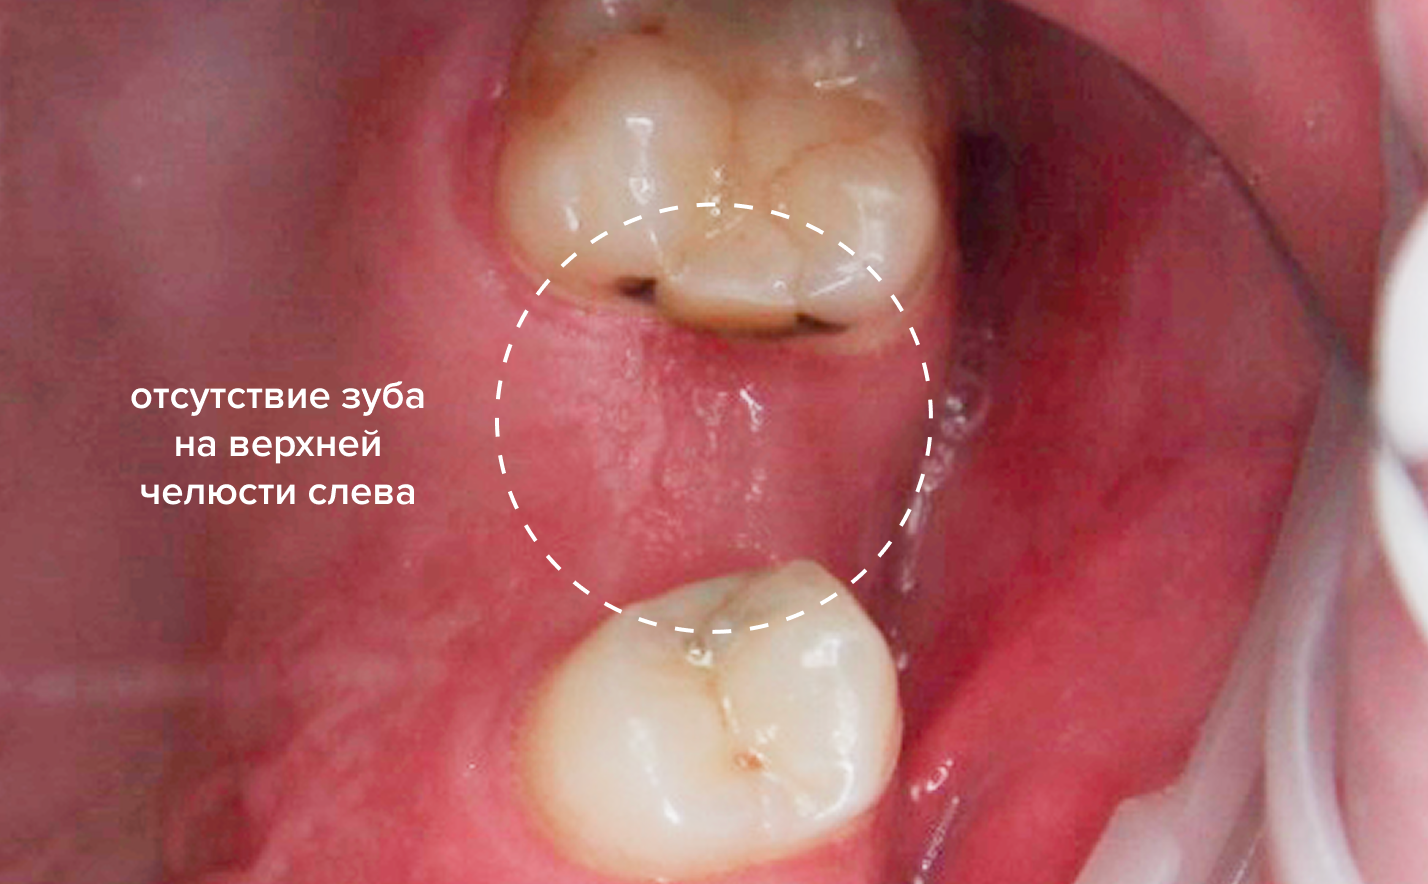

До и после

До

После